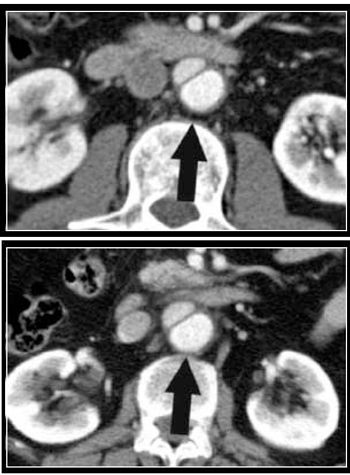

Korean researchers tested the ability of radiologists to spot CT images altered with commercially available software to introduce pathology and found that their skill is no more certain than the toss of a coin.

Korean researchers tested the ability of radiologists to spot CT images altered with commercially available software to introduce pathology and found that their skill at doing so is no more certain than a coin flip.

Korean researchers tested the ability of radiologists to spot CT images altered with commercially available software to introduce pathology and found that their ability to do so is no more certain than a coin flip.